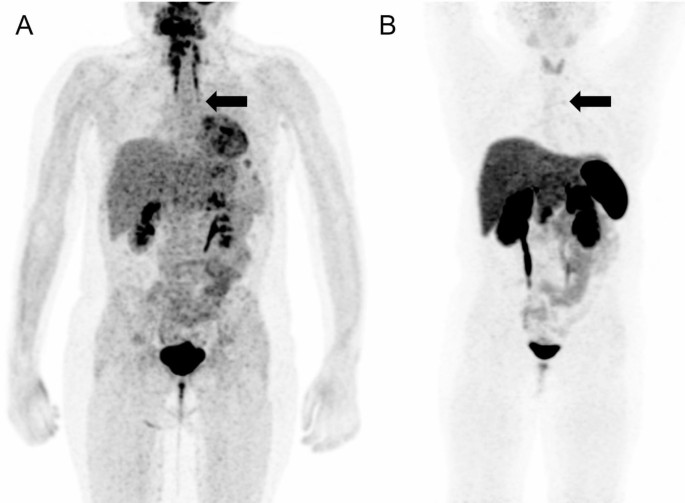

Figure 4: Clinical course between hospitalization and cesarean delivery

(A) Blood pressure trend, (B) total dose of insulin, and (C) urinary free cortisol trend.